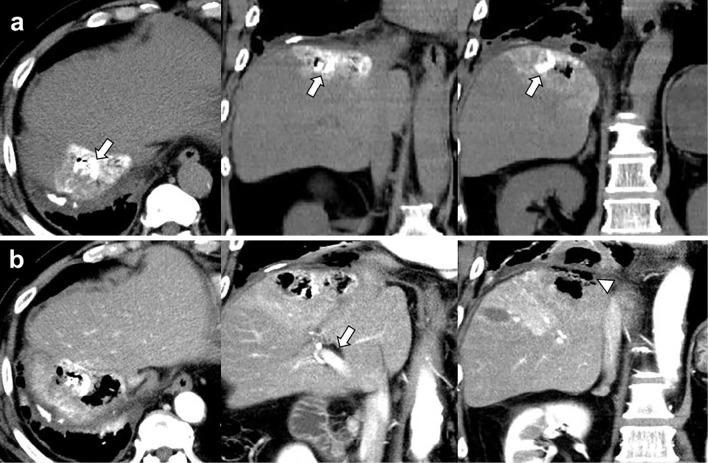

经皮射频消融治疗肝细胞癌后并发肝脓肿和胆支气管瘘的支气管腔内 Watanabe 分叉管置入术。

Endobronchial Watanabe Spigot Placement for Hepatic Abscess and Bronchobiliary Fistula Following Radiofrequency Ablation for Hepatocellular Carcinoma.

A bronchobiliary fistula (BBF) is an uncommon but severe complication after radiofrequency ablation (RFA). However, the definitive salvage methods are controversial. We herein report a patient with hepatocellular carcinoma with hepatic abscess and BBF following RFA. We also review previous reports of BBF after RFA. The patient was a man in his 70s who underwent RFA for recurrent hepatocellular carcinoma in the subphrenic area. Despite percutaneous transhepatic abscess drainage, bilioptysis persisted. Finally, the BBF was occluded with an endobronchial Watanabe spigot under fiber-optic bronchoscopy. Placing an endobronchial Watanabe spigot should be considered as a salvage therapy for refractory BBF following RFA.

摘要

支气管胆瘘(BBF)是射频消融(RFA)后一种罕见但严重的并发症。然而,明确的补救方法存在争议。我们在此报告一例 RFA 后肝脓肿和 BBF 的肝细胞癌患者。我们还回顾了 RFA 后 BBF 的以往报告。患者为 70 多岁男性,因膈下区复发性肝细胞癌接受 RFA 治疗。尽管经皮经肝脓肿引流,但仍存在胆汁漏。最终,在纤维支气管镜下通过支气管内渡边塞子闭塞 BBF。对于 RFA 后难治性 BBF,放置支气管内渡边塞子应被视为一种补救治疗方法。